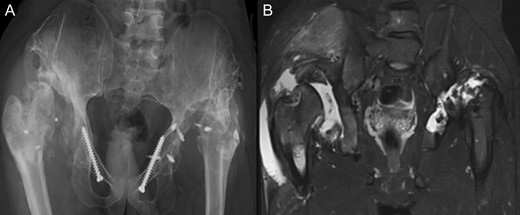

At this stage patient’s walking ability was already limited due to muscle weakness and rubbing in the hip joints, so we recommended no further walking and weight bearing. Further follow-up at 5 years (Fig. 7) and 10 years (Fig. 8A) until today showed radiologically complete absorption of the left femoral head and the right hip continuously moving cranially creating a false acetabulum and a flattened femoral head. At final follow up the patient was in a wheel chair but able to bend both hips up to 110 degrees without noticeable pain, he could stand up with help for a short time and showed a massive Charcot joint with effusion (Fig. 8B) of the right hip without further clinical implications.

(A + B): (2019) (A) x ray of the pelvis after a 10 year follow up. The right head further migrated und subluxated and femoral head necrosis is visible, new bone formation at the ileum stabilizing the joint. At the left side high dislocation of the hip with fully necrosis of the head and ankylosis of the hip joint. (B) MRI showing hip effusion around the joint which is painless.